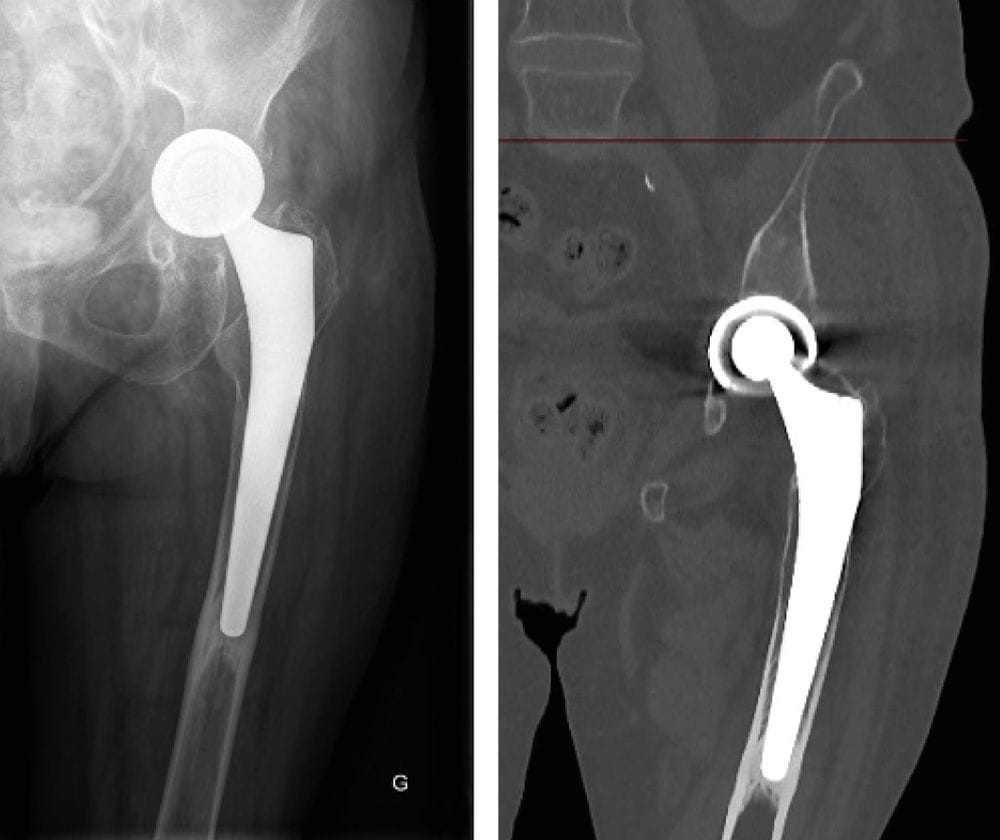

- Acetabular loosening with implant migration? (Figure 7)

One-stage revision: (Figure 8)

- Acetabular reconstruction with Kerboull cross-plate + bone graft

- Femoral window fixed with cerclage wiring

- Locking long stem and weight-bearing from day 1

- MSSA treated with Oflocet + Rifadin

Recurrence of acute infection after 1 month: (Figure 9)

- Lavage and revision of moving parts

- Negative cultures on ATB

- Treatment with IV Claforan + Daptomycin via PICC line for 3 months

- Follow-up at 18 months OK